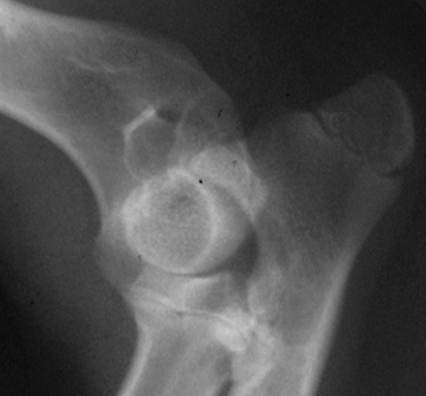

What is shown in these radiographs?

hypertrophic nonunion

-widening of fracture gap

-excessive, non-bridging callus

-sclerotic fracture ends

Q

A

oligotrophic nonunion

-rounded fracture ends

-sealed medullary cavity of distal fragment

-minimal callus formation

defect nonunion

-large fracture gap; callus cannot bridge

atrophic nonunion